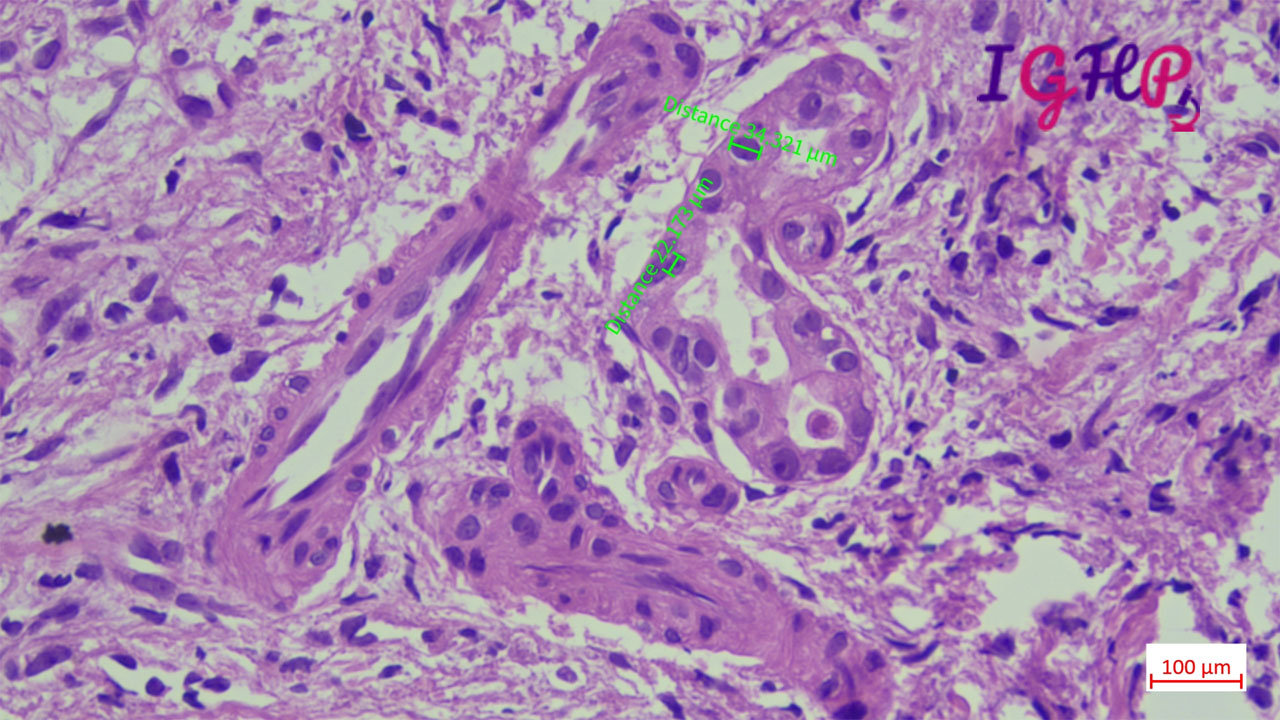

Microscopic Images-

Microscopic examination showed atypical bile ductular proliferation in dense sclerotic stroma. Areas of mild nuclear pleomorphism noted. Intraluminal apoptotic debris seen.

MT stain performed showed dense sclerotic desmoplastic stroma